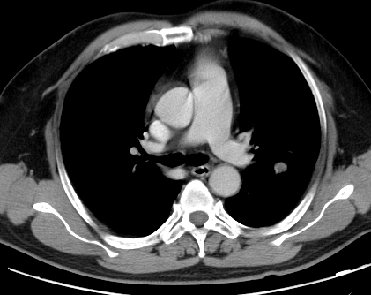

2016-06-13CT:

1、肠癌术后

2、肝左内叶结节,转移灶可能

3、左肺舌叶及左下肺后基底段结节,转移可能

2016-09-06CT:

2、肝左内叶上部转移灶缩小

3、左肺舌叶及左下肺后基底段结节变化不大

2016-10-24MR及CT:

1、肝左内叶转移灶缩小

2、肺结节变化不大